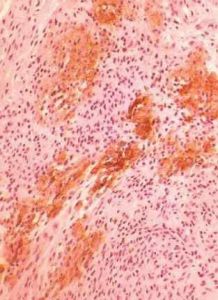

外陰纖維瘤鏡下可見平行的纖維索呈波浪狀或互相盤繞,實質由成熟的成纖維細胞和膠原纖維組成,呈束狀編織狀。細胞核呈梭形,有的地方可見黏液樣退行性變,無分裂象,包膜為纖維結締組織,表面分葉不規則,光滑,質硬。切面為緻密灰白色纖維組織,呈束狀縱橫交錯排列或呈漩渦狀排列。間質一般更緻密,膠原纖維多,即纖維瘤切面呈緻密的、堅硬而灰白色的纖維結構。

外陰纖維瘤鏡下可見平行的纖維索呈波浪狀或互相盤繞,實質由成熟的成纖維細胞和膠原纖維組成,呈束狀編織狀。

細胞核呈梭形,有的地方可見黏液樣退行性變,無分裂象,包膜為纖維結締組織,表面分葉不規則,光滑,質硬。間質一般更緻密,膠原纖維多,即纖維瘤切面呈緻密的、堅硬而灰白色的纖維結構。